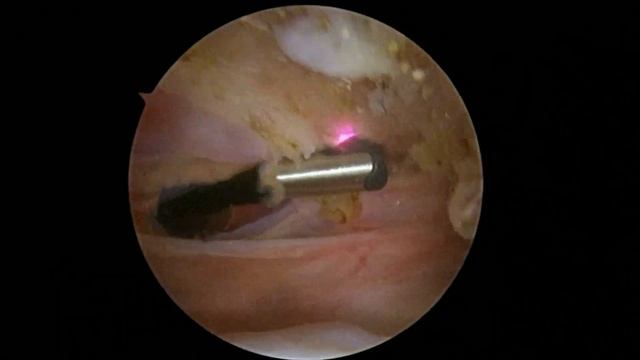

R Suprapectoral Biceps Tenodesis 8 4 22 WE